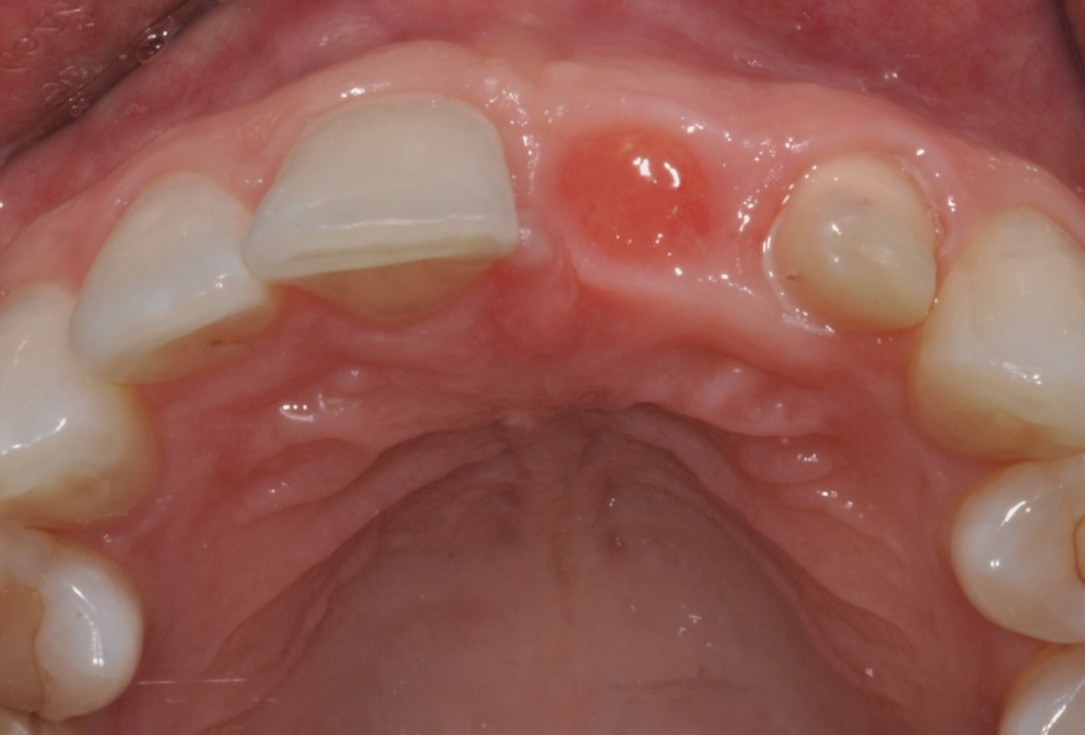

02/16 - Situation before extraction, occlusal view

Socket preservation with cerabone® - Dr. R. A. Nader